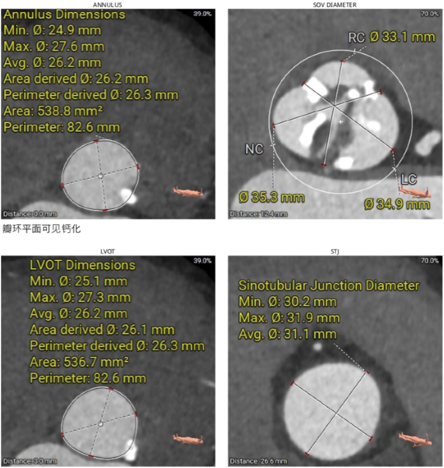

2)患者主动脉根部结构复杂,为Type 2型二叶瓣畸形,左右对合缘、右无对合缘处均可见钙化融合嵴,瓣环平面可见严重钙化,左冠窦底钙化灶延伸至左室流出道,且左室腔小。

瓣叶钙化严重,且增厚增长。